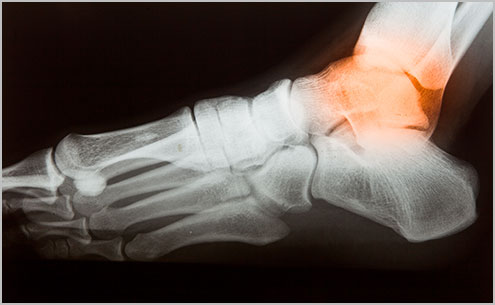

Àδë(Ligament)´Â °üÀýÀ» ¾ÈÁ¤ÈÇÏ°í ´Ü´ÜÇÏ°Ô ÇÏ´Â ¿ªÇÒÀ» Çϸç, °üÀýÀ» Á¤·ÄÇÏ¿© À¯ÁöÇØ ÁÖ°í, °üÀýÀÇ ¿òÁ÷ÀÓÀ» Á¤»ó ¹üÀ§ ³»¿¡¼¸¸ µÇµµ·Ï Á¦ÇÑÇÕ´Ï´Ù. ÀÌ·¯ÇÑ ±â´ÉÀ» ÇÏ´Â Àδ밡 »ç°í³ª ¿Ü»ó µî¿¡ ÀÇÇØ ¼Õ»óµÈ °ÍÀ» ¿°Á¶ó°í Çϸç ÈçÈ÷ "»ß¾ú´Ù" ¶ó°í ¸»ÇÕ´Ï´Ù. ¿°Á°¡ »ý±â¸é Àδ밡 Âõ¾îÁö°Å³ª ´Ã¾î³ª °üÀýÀ» À¯ÁöÇÏ´Â Á¦¿ªÇÒÀ» ÀÒ°Ô µÇ°í ÀÌ·Î ÀÎÇØ Á¤»óÀûÀ¸·Î °üÀýÀ» À¯ÁöÇÒ ¼ö ¾ø°Ô µË´Ï´Ù. ½ÉÇÏ¸é ¿°ÁÂµÈ °üÀýÀÌ ´Ã¾î³ª¼ »À°¡ Å»°ñµÇ°Å³ª °üÀýÀÌ Á¤»ó ¹üÀ§ ¹ÛÀ¸·Î ¹þ¾î³ª±âµµ ÇÕ´Ï´Ù.

°üÀýÀÌ ¿°Á嵃 °æ¿ì Àδ밡 ²¿¾ÆÁö°Å³ª ´Ã¾î³ª¸é Á¤»óÀûÀ¸·Î °üÀýÀ» À¯ÁöÇÒ ¼ö ¾ø°Ô µË´Ï´Ù. ½ÉÇÏ¸é ¿°ÁÂµÈ °üÀýÀÌ ´Ã¾î³ª¼ »À°¡ Å»°ñµÇ°Å³ª °üÀýÀÌ Á¤»ó ¹üÀ§ ³»¿¡¼ ¹þ¾î³ª±âµµ ÇÕ´Ï´Ù. ¾ÐÅë°ú ´õºÒ¾î ¼Õ»óµÈ °üÀý¿¡ µ¿Åë°ú ºÎÁ¾À» À¯¹ßÇÕ´Ï´Ù. Áߵ ȤÀº ½ÉÇÑ ¿°ÁÂÀÇ °æ¿ì °üÀýÀÇ ¸ð¾çÀÇ º¯È¿Í °üÀý ±â´ÉÀÇ º¯È¸¦ °¡Áö°í ¿Ã ¼ö ÀÖ½À´Ï´Ù. ÀÌ·¯ÇÑ ±â´ÉÀÇ º¯È¿¡´Â °üÀýÀÌ ºÒ¾ÈÁ¤ÇÑ ´À³¦À̳ª ºÒÆíÇÑ ´À³¦, °üÀýÀÌ ³Ê¹« Çæ°Ì´Ù°í ´À²¸Áö°Å³ª, »À°¡ Á¦ À§Ä¡¿¡ ÀÖÁö ¾ÊÀº ´À³¦, °üÀýÀÌ Á¤»ó ¿òÁ÷ÀÓÀ» ¹þ¾î³ ´À³¦ÀÌ µì´Ï´Ù.